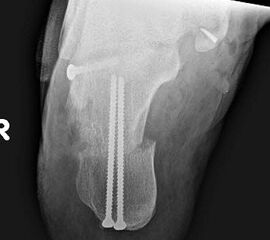

Radiologisches Beispiel einer fixierten Planovalgus Deformität Stadium III, 51 jähriger Patient. Stehendes präoperatives Röntgenbild und 1 Jahr postoperatives Röntgenbild des Fußes seitlich. Die Korrektur der Deformität umfaßte eine leicht korrigierende U

Abbildung 12

Im Stadium III der Tibialis posterior Sehneninsuffizienz bei fixierter Deformität und/oder erheblich eingeschränkter Inversion im USG aber stabilen und flexiblen Chopart-Gelenk und weniger als 10° fixierter Vorfußsupination eine in-situ oder leicht korrigierende USG-Arthrodese indiziert. Der Vorteil einer isolierten USG-Arthrodese gegenüber einer Triple- oder Double-Arthrodese ist die verbleibende, funktionell wichtige Beweglichkeit in der Chopart-Gelenkreihe. Um einem persistierenden fibulocalcanearem Impingement sicher vorzubeugen, sollte die USG-Arthrodese in maximal 5° Valgus- oder sogar Neutralposition erfolgen. Zur Prophylaxe eines Rezidivs wird die USG-Arthrodese zudem häufig mit einer medialisierende Tuber calcanei Osteotomie und / oder einem FDL-Transfer kombiniert (Abb. 12).